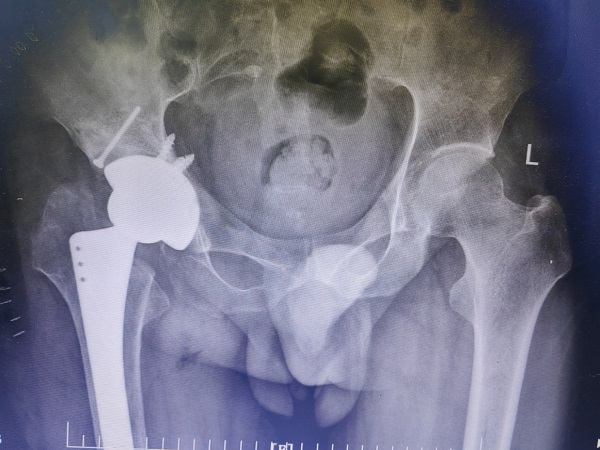

为了顺利手术,在完善髋臼骨缺损的垫块、异体股骨头等结构性植骨材料、陶对陶全髋关节假体的准备后,郭永良主任医师主刀,王争刚主任医师等辅助,历时2小时,手术顺利完成。术后患者双下肢等长,无神经、血管损伤。目前术后三周,患者可扶拐逐渐负重下地行走,相信经过一段时间的康复和锻炼,李师傅可再次回归社会,恢复正常的生活和工作。